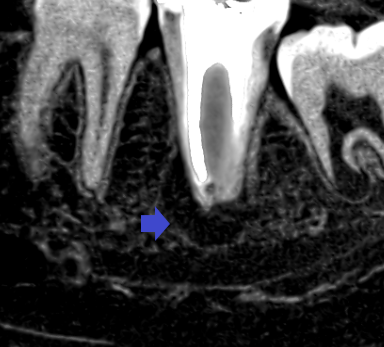

下顎第二大臼歯の初診時の冠状断のCT画像です。

赤い矢印の先に下顎骨を破りそうな位大きくなった膿の影がみられます。青い矢印の先は、下顎管という太い神経の通り道です。下顎管に達するくらいの大きな膿です。ここまで膿が大きいと一般的には、抜歯を勧められると思います。